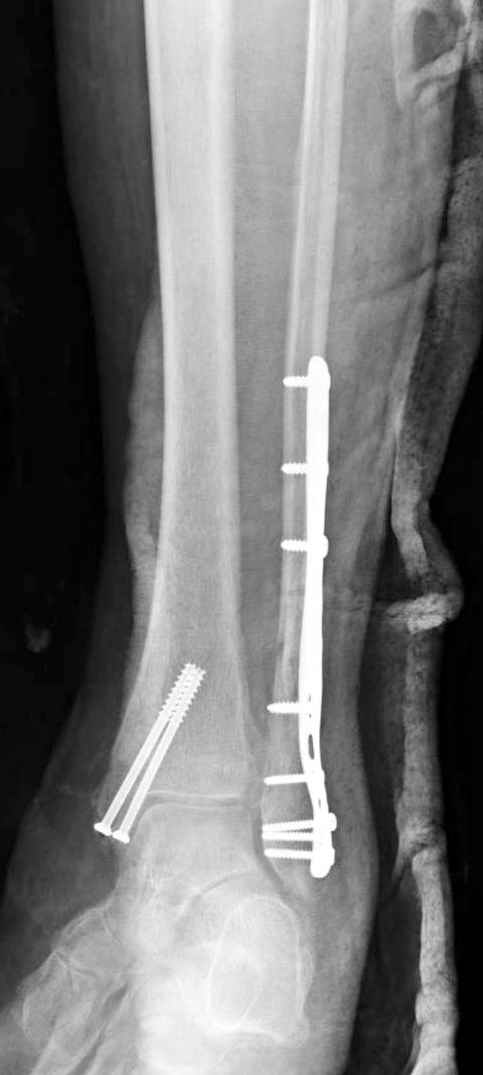

На 4-й неделе убрал спицы, с 7-й недели начал ЛФК, дозированную нагрузку, физиопроцедуры, массаж. Назначил хондропротекторы. Получилось вот что.

Rg-05.JPG

Удалены спицы, а гипса не было? 3-х лодыжечный перелом фиксировать 4 недели недостаточно. Что и подтверждается на последнем снимке - есть тенденция к подвывиху кнаружи, кзади... Что будет дальше, когда пациент начнет давать полную нагрузку?

Малоберцовая выглядит коротковатой. Профиль как-то мутный. Вообще, неплохо было бы сделать снимки в сравнении со здоровой.